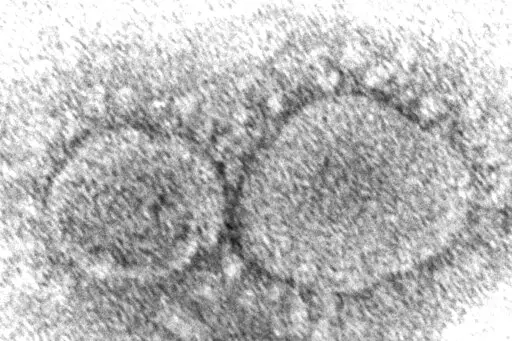

Workers at a drive-up COVID-19 testing clinic stand in a tent as they prepare PCR coronavirus tests, Jan. 4, 2022, in Puyallup, Wash., south of Seattle. Testing for COVID-19 has plummeted across the globe, dropping by 70 to 90% worldwide from the first to the second quarter of 2022, making it much tougher for scientists to track the course of the pandemic and spot new, worrisome viral mutants as they emerge and spread. (AP Photo/Ted S. Warren, File)